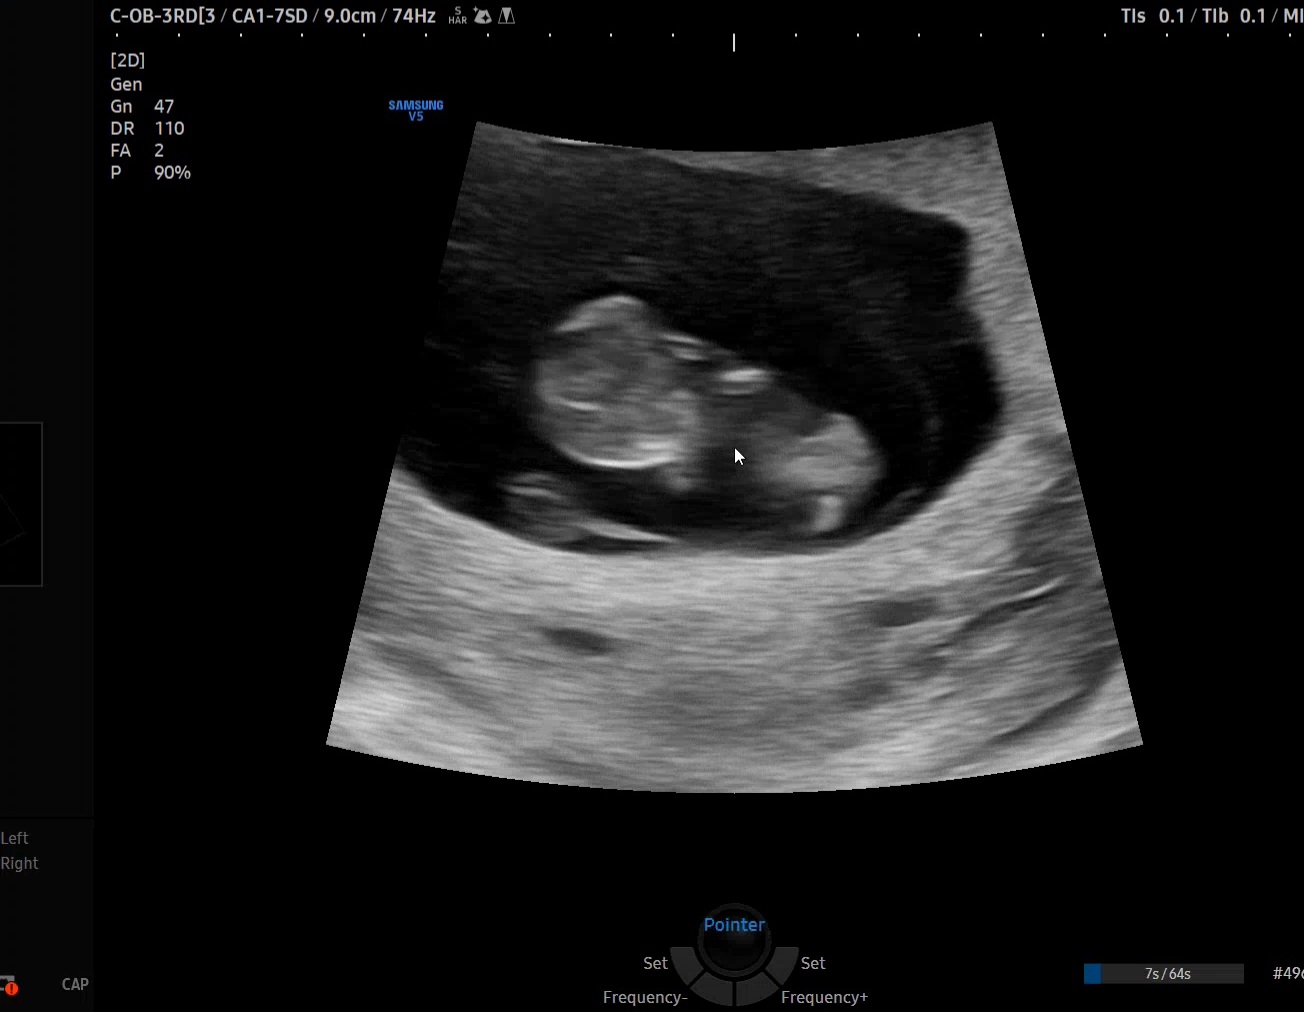

9주6일 초음파에용

너무 귀여워요ㅜㅜ 아니 다른분들도 이맘때쯤 초음파 보실 때 아기가 엄청 움직이나여??? 동영상보면 진짜 계속 꿈틀거리고 움직여서 원장님께서는 이미 튼튼하다고 안정기라고 보면 되겠다고 하시고, 저희 엄마는 너무 귀엽다며 니보다 별난 애가 나올란갑다ㅋㅋㅋ 하시네용ㅋㅋㅋㅋ 입덧도 초반에 약간 먹덧?체덧?인가..? 할 정도로 약하게 왔다가 지금은 약간의 두통 말고는 컨디션도 좋아요!! 다들 젤리곰 초음파때 많이 움직였나욤??